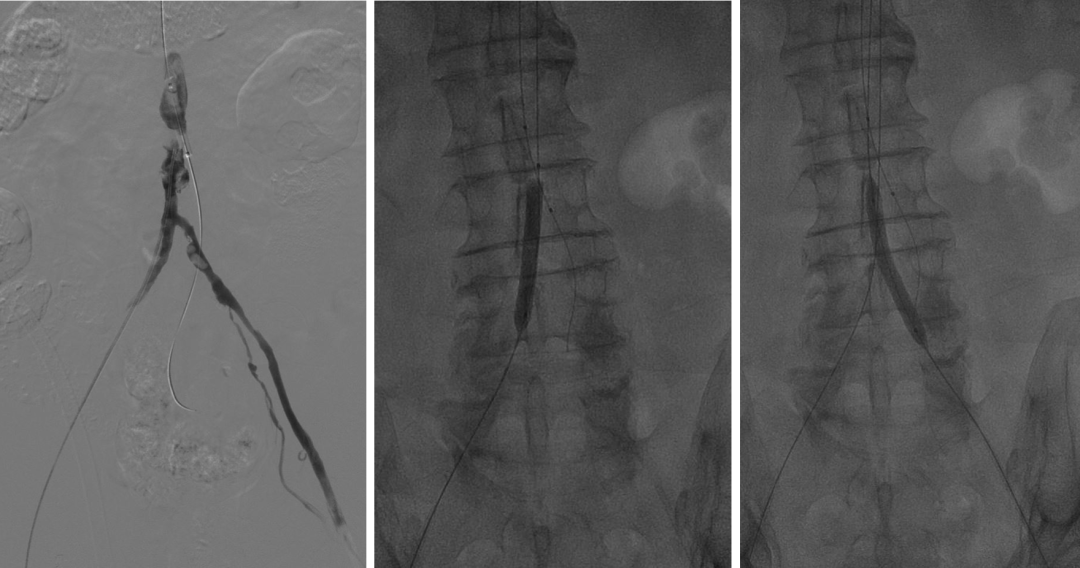

支架选择:采用球扩式ePTFE覆膜支架(如Advanta V12或Atrium Medical),直径15-20mm,长度12mm。

操作路径:可经股动脉或肱动脉入路,需双侧支架对吻释放(模拟解剖分叉)

治疗策略:复合手术(双侧股动脉切开取栓 + CERAB),兼顾血栓清除与长期血管重建。

左侧肱动脉入路,主髂动脉造影

双侧股动脉切开,经股动脉7F Fogarty导管取栓

术后结果:ABI改善,症状缓解,无围术期并发症